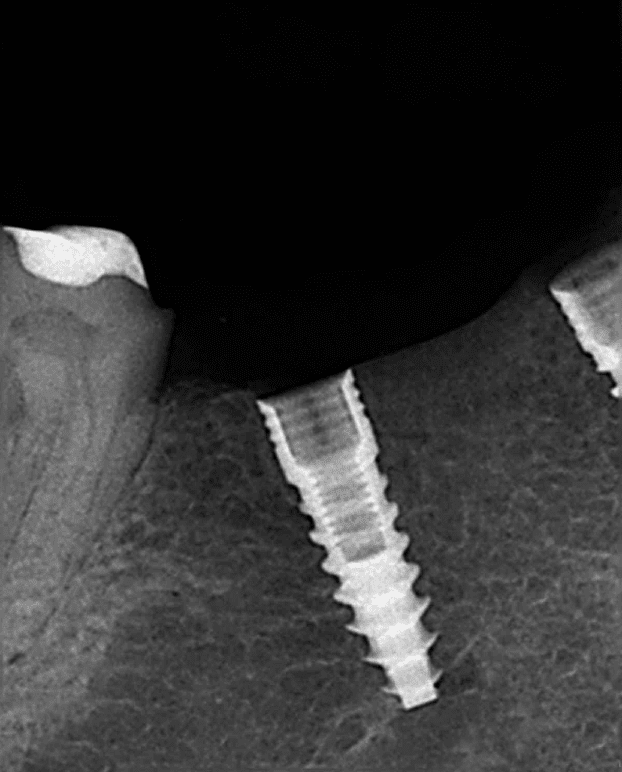

Xray of a dental implant screwed into the jaw boneThe screw threads on this dental implant are clearly visible

When an implant is first put in, it is literally screwed into place. The dentist drills a pilot hole first, and then screws the implant into the hole.

At this point, the only thing holding the implant into your jawbone is the screw thread. It's similar to screwing a wood screw into a block of wood. The dentist will normally use a miniature surgical torque wrench to screw the implant into place.

There should be enough good solid bone to need a specific force (torque) to get the implant into position. If the implant simply turns and turns, going into place easily without needing any effort (enough "torque) then it will not be stable enough for proper osseo-integration.

We want the implant to be firmly anchored in there, so that the magic process of osseo-integration can take place, literally fusing the implant to the bone.

BUT, if there is ANY movement at all, the fusing process is likely to fail. Professor Branemark identified this as a reason for failure more than 50 years ago, when he was developing the technique!

Even TINY movements, called "micromovement" can interfere with the integration of the implant. Preventing micromovement is critical to the success of any dental implant.

The MAIN cause of micromovement is that the bone around the implant is too soft, too weak, or simply there is not enough bone to support the full length of the implant. It's like trying to screw a one inch wood screw into a piece of wood only half an inch thick. You end up with half the screw still sticking out.